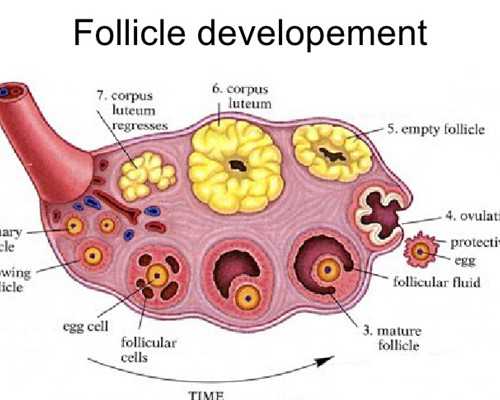

2.雌二醇很低到底有沒有關系,試管嬰兒,移植后

1)雌二醇偏低最直接的危害是導致女性不孕,因為它主要激發卵泡發育,同時血清雌二醇水平也間接上影響了卵巢功能,偏低則導致不排卵,影響生育;(2)女性的子宮、外陰、生殖道等器官的發育需要各類雌激素,如果雌二醇等激素水平降低則最終導致,女性子宮、外陰、生殖道萎縮;(3)雌二醇過低還會造成女性子宮內膜變薄,最終影響到月經量,直接影響到卵泡發育誘發不孕癥,除此外雌二醇偏低還會造成身體上出現一些更年期癥狀,如情緒不穩、失眠、潮熱、出汗等。盡早治療對于雌二醇增高有很好的調理作用,一般可通過一些雄激素類藥物來促使雌二醇恢復到正常水平。在做試管嬰兒之前醫生會根據患者的具體報告來進行診斷,是否能夠進行試管也需要根據患者自身的水平進行考慮。

5.雌二醇很低到底有沒有關系,試管嬰兒,移植后

1)雌二醇偏低最直接的危害是導致女性不孕,因為它主要激發卵泡發育,同時血清雌二醇水平也間接上影響了卵巢功能,偏低則導致不排卵,影響生育;(2)女性的子宮、外陰、生殖道等器官的發育需要各類雌激素,如果雌二醇等激素水平降低則最終導致,女性子宮、外陰、生殖道萎縮;(3)雌二醇過低還會造成女性子宮內膜變薄,最終影響到月經量,直接影響到卵泡發育誘發不孕癥,除此外雌二醇偏低還會造成身體上出現一些更年期癥狀,如情緒不穩、失眠、潮熱、出汗等。盡早治療對于雌二醇增高有很好的調理作用,一般可通過一些雄激素類藥物來促使雌二醇恢復到正常水平。在做試管嬰兒之前醫生會根據患者的具體報告來進行診斷,是否能夠進行試管也需要根據患者自身的水平進行考慮。

6.雌二醇很低到底有沒有關系,試管嬰兒,移植后

1)雌二醇偏低最直接的危害是導致女性不孕,因為它主要激發卵泡發育,同時血清雌二醇水平也間接上影響了卵巢功能,偏低則導致不排卵,影響生育;(2)女性的子宮、外陰、生殖道等器官的發育需要各類雌激素,如果雌二醇等激素水平降低則最終導致,女性子宮、外陰、生殖道萎縮;(3)雌二醇過低還會造成女性子宮內膜變薄,最終影響到月經量,直接影響到卵泡發育誘發不孕癥,除此外雌二醇偏低還會造成身體上出現一些更年期癥狀,如情緒不穩、失眠、潮熱、出汗等。盡早治療對于雌二醇增高有很好的調理作用,一般可通過一些雄激素類藥物來促使雌二醇恢復到正常水平。在做試管嬰兒之前醫生會根據患者的具體報告來進行診斷,是否能夠進行試管也需要根據患者自身的水平進行考慮。

3.雌二醇很低到底有沒有關系,試管嬰兒,移植后

1)雌二醇偏低最直接的危害是導致女性不孕,因為它主要激發卵泡發育,同時血清雌二醇水平也間接上影響了卵巢功能,偏低則導致不排卵,影響生育;(2)女性的子宮、外陰、生殖道等器官的發育需要各類雌激素,如果雌二醇等激素水平降低則最終導致,女性子宮、外陰、生殖道萎縮;(3)雌二醇過低還會造成女性子宮內膜變薄,最終影響到月經量,直接影響到卵泡發育誘發不孕癥,除此外雌二醇偏低還會造成身體上出現一些更年期癥狀,如情緒不穩、失眠、潮熱、出汗等。盡早治療對于雌二醇增高有很好的調理作用,一般可通過一些雄激素類藥物來促使雌二醇恢復到正常水平。在做試管嬰兒之前醫生會根據患者的具體報告來進行診斷,是否能夠進行試管也需要根據患者自身的水平進行考慮。

5.雌二醇很低到底有沒有關系,試管嬰兒,移植后

1)雌二醇偏低最直接的危害是導致女性不孕,因為它主要激發卵泡發育,同時血清雌二醇水平也間接上影響了卵巢功能,偏低則導致不排卵,影響生育;(2)女性的子宮、外陰、生殖道等器官的發育需要各類雌激素,如果雌二醇等激素水平降低則最終導致,女性子宮、外陰、生殖道萎縮;(3)雌二醇過低還會造成女性子宮內膜變薄,最終影響到月經量,直接影響到卵泡發育誘發不孕癥,除此外雌二醇偏低還會造成身體上出現一些更年期癥狀,如情緒不穩、失眠、潮熱、出汗等。盡早治療對于雌二醇增高有很好的調理作用,一般可通過一些雄激素類藥物來促使雌二醇恢復到正常水平。在做試管嬰兒之前醫生會根據患者的具體報告來進行診斷,是否能夠進行試管也需要根據患者自身的水平進行考慮。

6.雌二醇很低到底有沒有關系,試管嬰兒,移植后

1)雌二醇偏低最直接的危害是導致女性不孕,因為它主要激發卵泡發育,同時血清雌二醇水平也間接上影響了卵巢功能,偏低則導致不排卵,影響生育;(2)女性的子宮、外陰、生殖道等器官的發育需要各類雌激素,如果雌二醇等激素水平降低則最終導致,女性子宮、外陰、生殖道萎縮;(3)雌二醇過低還會造成女性子宮內膜變薄,最終影響到月經量,直接影響到卵泡發育誘發不孕癥,除此外雌二醇偏低還會造成身體上出現一些更年期癥狀,如情緒不穩、失眠、潮熱、出汗等。盡早治療對于雌二醇增高有很好的調理作用,一般可通過一些雄激素類藥物來促使雌二醇恢復到正常水平。在做試管嬰兒之前醫生會根據患者的具體報告來進行診斷,是否能夠進行試管也需要根據患者自身的水平進行考慮。

8.雌二醇很低到底有沒有關系,試管嬰兒,移植后

1)雌二醇偏低最直接的危害是導致女性不孕,因為它主要激發卵泡發育,同時血清雌二醇水平也間接上影響了卵巢功能,偏低則導致不排卵,影響生育;(2)女性的子宮、外陰、生殖道等器官的發育需要各類雌激素,如果雌二醇等激素水平降低則最終導致,女性子宮、外陰、生殖道萎縮;(3)雌二醇過低還會造成女性子宮內膜變薄,最終影響到月經量,直接影響到卵泡發育誘發不孕癥,除此外雌二醇偏低還會造成身體上出現一些更年期癥狀,如情緒不穩、失眠、潮熱、出汗等。盡早治療對于雌二醇增高有很好的調理作用,一般可通過一些雄激素類藥物來促使雌二醇恢復到正常水平。在做試管嬰兒之前醫生會根據患者的具體報告來進行診斷,是否能夠進行試管也需要根據患者自身的水平進行考慮。

10.雌二醇很低到底有沒有關系,試管嬰兒,移植后

1)雌二醇偏低最直接的危害是導致女性不孕,因為它主要激發卵泡發育,同時血清雌二醇水平也間接上影響了卵巢功能,偏低則導致不排卵,影響生育;(2)女性的子宮、外陰、生殖道等器官的發育需要各類雌激素,如果雌二醇等激素水平降低則最終導致,女性子宮、外陰、生殖道萎縮;(3)雌二醇過低還會造成女性子宮內膜變薄,最終影響到月經量,直接影響到卵泡發育誘發不孕癥,除此外雌二醇偏低還會造成身體上出現一些更年期癥狀,如情緒不穩、失眠、潮熱、出汗等。盡早治療對于雌二醇增高有很好的調理作用,一般可通過一些雄激素類藥物來促使雌二醇恢復到正常水平。在做試管嬰兒之前醫生會根據患者的具體報告來進行診斷,是否能夠進行試管也需要根據患者自身的水平進行考慮。